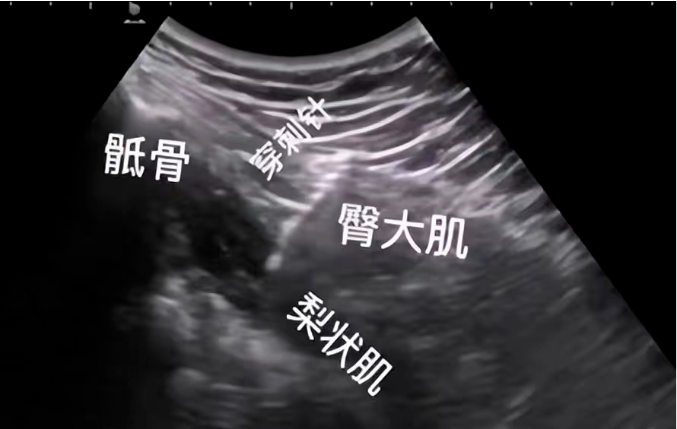

疼痛科团队,采用可视化技术详细检查梨状肌的水肿情况,并在肌骨超声的引导下将消炎镇痛液注入梨状肌病变组织周围。通过一次肌骨超声引导的注射治疗,患者臀部疼痛明显减轻、髋关节功能得到明显改善。

(图为超声可视化技术引导注射治疗)